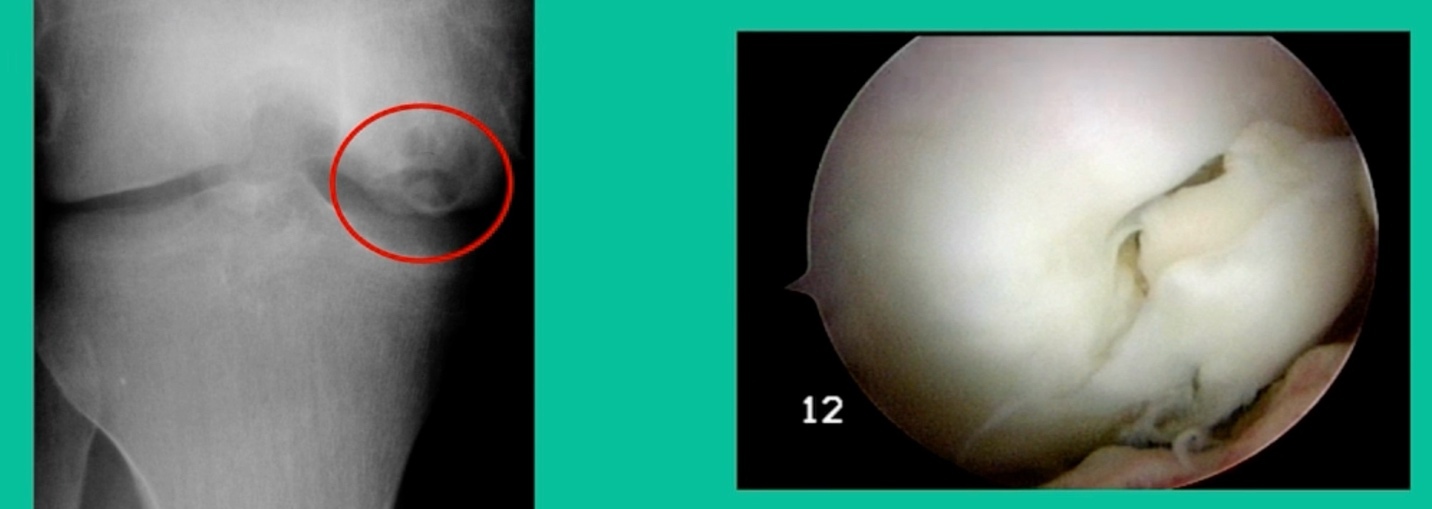

Now a couple of quick cases. This is juvenile OCD. This is the first series of three or four, just juveniles. 14-year-old, intermittent knee pain, lateral femoral condyle OCD (Figure 1).

I thought I might be able to fix it. I had the conversation with the family, get in there, started taking it apart with a Vanguard elevator grasper. Behold, it’s really just cartilage fragments (Figure 2).

There’s two or three of them. We debrided it. It felt normal in six weeks, no complaints in three years. What are the results of juvenile debridement? They’re actually profoundly good. You would never expect this in the scheme of things, but the natural history of removing the piece is actually very good in the juvenile patient. However, once again, fix it if you can. Debride it, if you can’t. If they get symptoms, we restore it, and then never leave unstable fragments.

This is an 11-year-old. Left knee lateral knee pain. Effusions, the same type of classic findings (Figure 3)

You look at this one, you say, “what are you going to see when you get in there?” This is one when you get in there, you say, I’m not even sure I’m in the right knee because you almost don’t see it. That happens in patients who were painful, but they don’t look macroscopically unstable. Pediatric orthopedic surgeons tend to drill these. These are the ones that I see as failures. I think when you’re talking about something that’s mechanically unstable, it’s hard to understand why drilling would actually make it work without fixation. Even if it’s microscopically unstable.